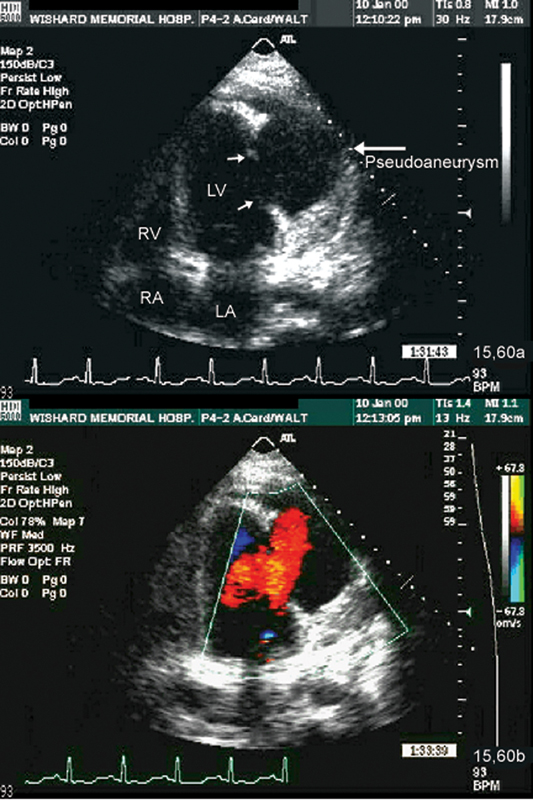

فحوصات تشخيصية لبعض امراض القلب والشرايين التاجية